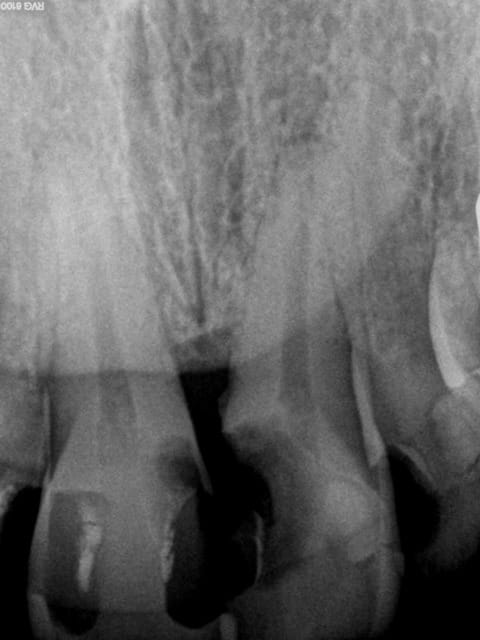

chicot29

05/02/2015 à 15h48

> Honnêtement, la dent est quand même bien niquée !

> Fêlure mesiale et distale, le curetage n'est pas complet sur l'arrête restante.

Je fais aussi souvent des couronnes sur dents vivantes . Par contre dans le cas present , j'y reflechirai à deux fois : grosse obturation, nombreuses felures (atteinte pulpaire ?) et retraction pulpaire +++ .

N'as tu jamais eu des réactions apicales aigues suite à la pose d'une couronne sur de telles dents ?